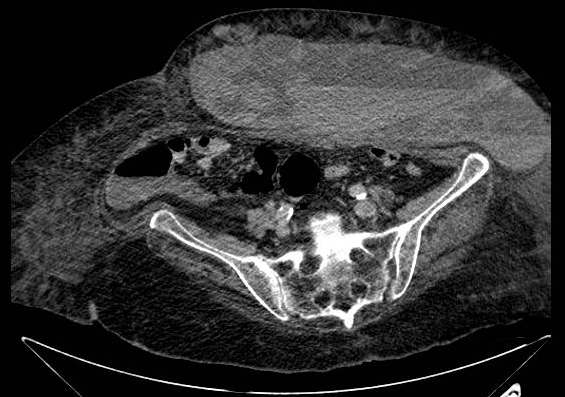

Case Presentation: An 88-year-old female with hypertension was admitted to the hospital due a to right tibiofibular fracture and underwent an open reduction internal fixation (ORIF). During admission, she was diagnosed with heart failure with preserved ejection fraction (>55%) and non-valvular atrial fibrillation with CHA2DS2-VASc score 5. She was started on therapeutic anticoagulation therapy for cardioembolic event prevention with enoxaparin 60 mg subcutaneously every 12 hours. One day during rounds, the patient began complaining of new, worsening left‐sided abdominal pain at the enoxaparin injection site associated with drowsiness, diaphoresis and fatigue. Physical examination and laboratories were remarkable for tachycardia, hypotension, a distended abdomen with generalized tenderness and a left upper quadrant area of induration and bruising associated with a hemoglobin drop from 9.3 g/dL to 5.4 g/dL. A diagnosis of hypovolemic shock was made and patient was resuscitated with intravenous fluids, packed red blood cells, and vasopressors. Abdominopelvic CT scan with contrast showed a large subcutaneous mixed density hematoma (2.9 cm x 7.6 cm x 10 cm) at the lower abdominopelvic wall with a hyperdense punctate focus within the hematoma suggestive of active bleeding. There was no identifiable source of bleeding and the left epigastric artery showed a normal course and caliber without evidence of extravasation of contrast to the hematoma. The patient was stabilized and transferred to intensive care unit for further hemodynamic support and close monitoring. Interventional Radiology and General Surgery services were consulted for acute management, but despite aggressive measures, the patient died of progressive bleeding during her ICU stay.